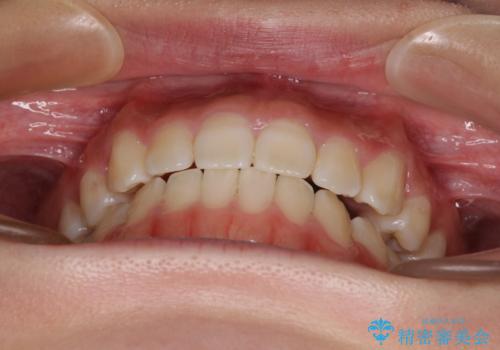

上顎骨を拡大することで、八重歯やデコボコを歯列に収めることができ、下顎の歯が外に位置していた奥歯の咬み合わせも改善することができました。

スペースも短期間に獲得できるため、1年程度で治療を終えることができました。